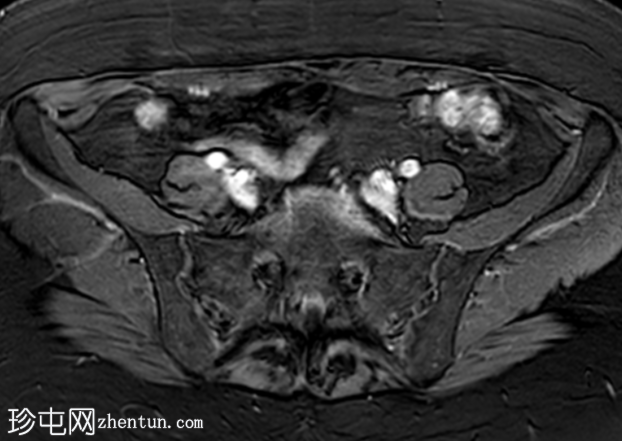

轴位T2加权像

脂肪抑制像

盆腔MRI显示左侧骶前区有两个小囊性病变,位于左侧附件的预期解剖位置。

病变在T2加权像上呈高信号,边界清晰,囊壁轻度增厚,光滑。在T1加权脂肪抑制像上,一个病变内部呈高信号,另一个病变呈低信号。静脉注射对比剂后,可见轻度周边囊壁强化,未见强化的实性成分。

未见扩散受限。病灶与邻近盆腔血管关系密切,无周围炎症改变、盆腔淋巴结肿大或游离液体的证据。

在术后盆腔中,MRI 对于病灶的定性尤为有用。典型的影像学特征包括位于预期卵巢解剖位置的囊性或混合性囊实性病变,通常与盆腔血管紧密相邻。常见的影像学特征包括 T2 高信号、T1 信号强度因出血或蛋白含量而异、轻度周边强化以及无扩散受限。

本例中,患者既往有双侧卵巢切除史,左侧附件预期位置出现小囊性病变,其中一个病变内含血性物质,且有轻度周边强化,支持卵巢残留组织的诊断。由于无扩散受限或侵袭性影像学特征,因此恶性肿瘤等其他诊断的可能性较小。